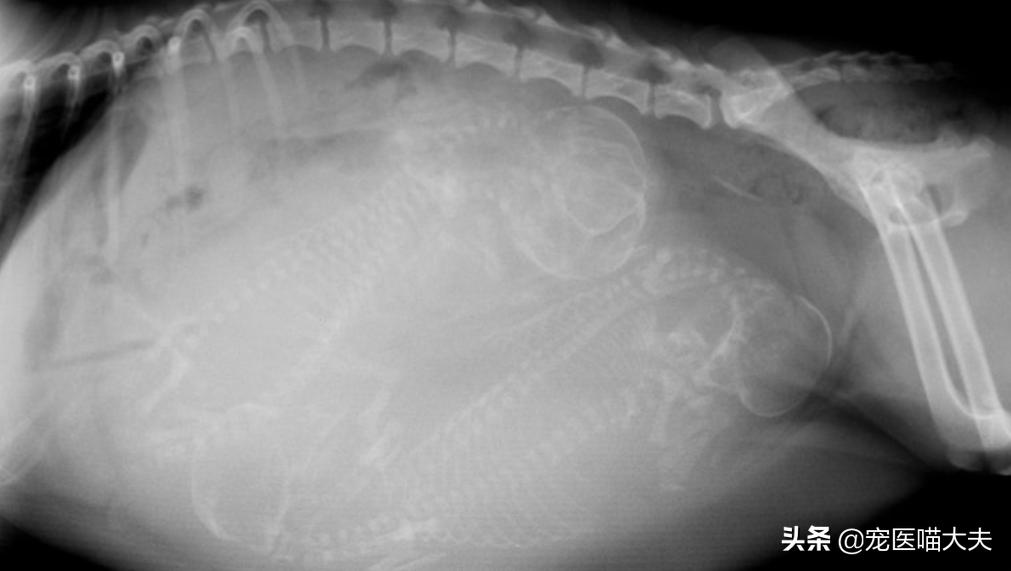

3、X射线检查

X射线检查一般用在雌性狗狗的怀孕后期,通过X射线检查,可以大约判断出狗妈妈子宫内小狗的数量;一般在55天之后进行X射线检查才可以准确判断出小狗的数量,因为在其之前,胎儿的颅骨和脊柱正在发育,且在X片上不可见,所以,对狗狗进行X射线检查时,掌握时间是非常重要的哦;另外,通过X射线检查也可判断狗狗是否有胎儿性难产或母体性难产的风险,比如胎儿是否过大和狗妈妈盆骨是否过窄等。

X射线检查怀孕的狗狗

第二个月(阶段),胎儿也是在这个月迅速发育,当胎儿发育到第32天的时候,就会形成眼睑,第35天的时候形成脚趾,第40天的时候形成爪子,45天后,就会逐渐形成骨骼和皮肤;当胎儿发育到第50天的时候,X射线检查就可以相对准确的判断出小狗数量了,而且,在第58天左右的时候,狗妈妈就会开始寻找“筑巢”的地方。